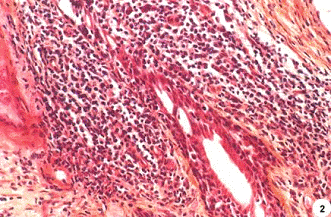

Рис. 2.

Околожелезистое хроническое воспаление. Плотные, сливающиеся лимфатические узлы окружают и инфильтрируют отдельные атрофированные участки железы.